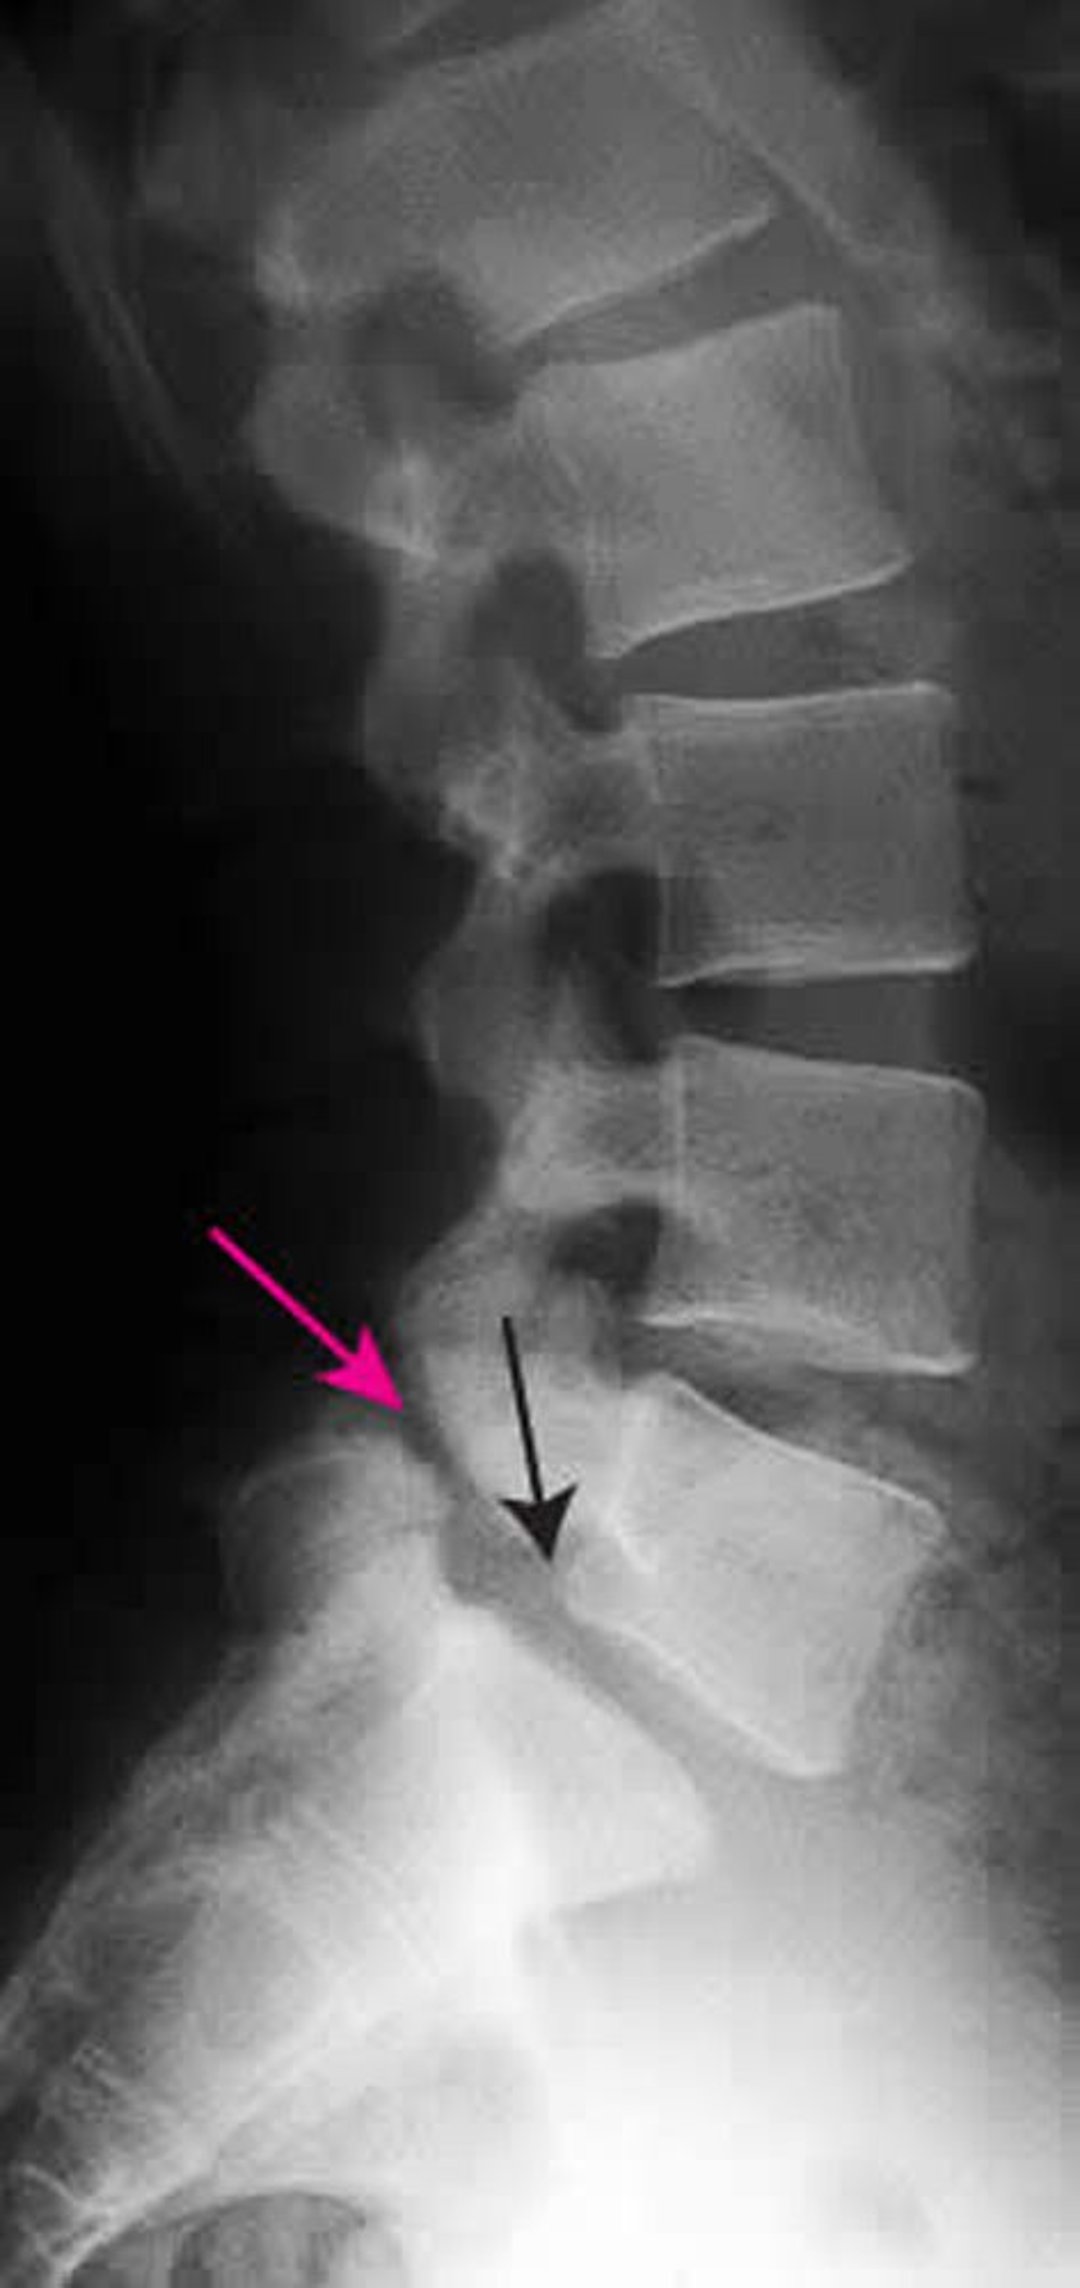

Spondylolisthesis is evident on radiographs of the lumbar spine. The lateral view is usually used for grading. Flexion and extension views may be done to check for increased angulation or forward movement.

Spondylolisthesis is graded according to the percentage of vertebral body length that one vertebra subluxes over the adjacent vertebra (1):

• Grade I: 0 to 25%

• Grade II: 25 to 50%

• Grade III: 50 to 75%

• Grade IV: 75 to 100%